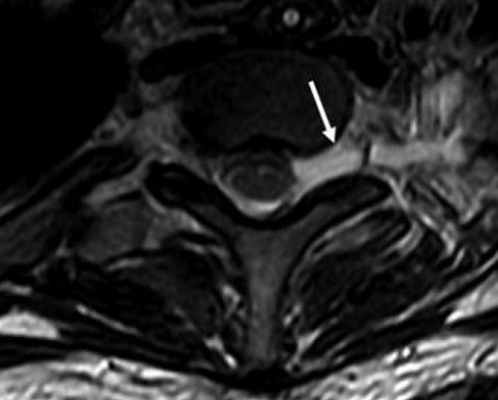

МРТ шейного отдела позвоночника. Аксиальная Т2-взвешенная МРТ. Псевдоменингоцеле.

При МРТ в СПб нам встречаются в в наших клиниках травматические его повреждения и заболевания. Травматические повреждения могут быть преганглионические (повреждение корешка) и постганглионические (повреждение ствола). Преганглионические, такие как псевдоменингоцеле, имеют хороший прогноз и лечатся обычно консервативно. Постганглионические повреждения требуют хирургического лечения. Псевдоменингоцеле хорошо видно при МРТ шейного отдела позвоночника.

Повреждения дистальнее корешка видны при МРТ мягких тканей шеи. Повреждение ствола видно как его разрыв и гиперинтенсивность на Т2-взвешенных МРТ.